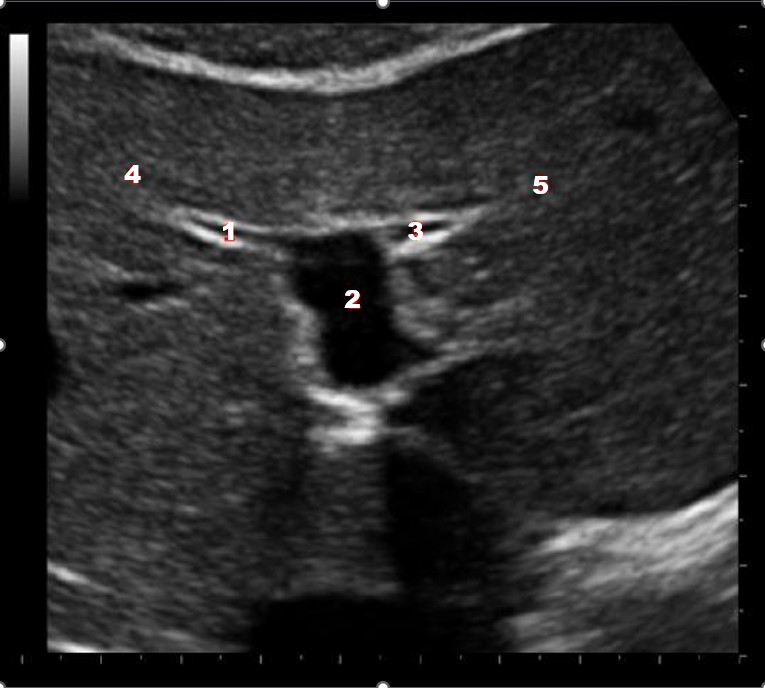

Which of the following structures is labeled number #1?

Left hepatic vein

Which of the following structures is labeled #2?

Middle hepatic vein

Which of the following structures is labeled #3?

IVC

Which of the following structures is labeled #4?

Right hepatic vein

Which of the following structures is labeled #8?

Posterior right lobe